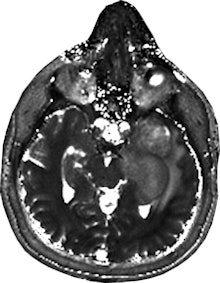

Dr. Siegfried Trattnig sees a "paradigm shift" from qualitative to quantitative imaging. Image courtesy of Medical University of Vienna/E. Hammerschmid.The results using an advanced MR imaging protocol and MR fingerprinting showed that the T1 and T2 mapping of tissue provided by fingerprinting was "better visualized" than in the standard protocol, said Trattnig, medical director of the university's Centre of Excellence in High Field MR and the chairman of the European Imaging Biomarkers Alliance (EIBALL). The testing was conducted using five patients with malignant brain tumors and an equal number with low-grade gliomas.

"It's my impression that we see more changes by using MR fingerprinting based on T1 and T2 maps on this quantitative data. And looking into the tumor, you see more details that are not shown on standard imaging," he explained, emphasizing that the results of the Austrian university's 2015 tests are only preliminary.

MR fingerprinting could be advantageous in other ways. Preliminary results suggest that there was low variability of the T1 and T2 relaxation times over multiple examinations of volunteers in Vienna, with the potential to accurately monitor and evaluate the progress of treatment, or even provide clues in the early detection of cancer. In addition, fingerprinting may also yield cost savings because of the reduced mapping time involved, and it is based on software that can be added to existing MR equipment, said Trattnig.